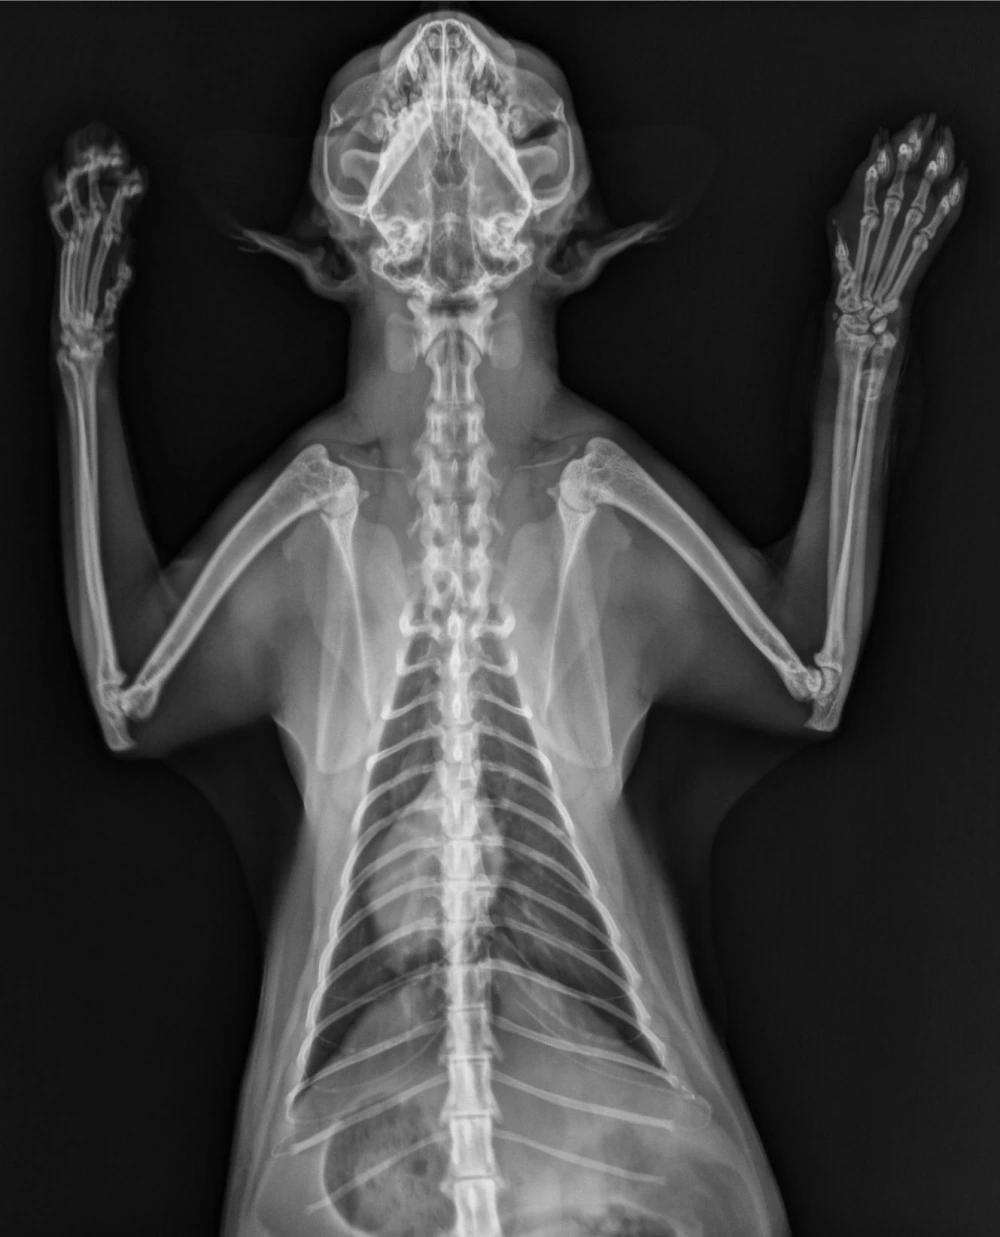

A radiografia torácica cães é um exame fundamental para a avaliação da saúde pulmonar e cardíaca desses animais.

Por meio desse procedimento, é possível identificar diversas condições médicas, como pneumonias, edemas pulmonares, colapsos traqueais, cardiomegalias e até mesmo a presença de corpos estranhos no trato respiratório.

A radiografia torácica cães é indicada em casos de tosse crônica, dificuldade respiratória, quadros de dispneia, suspeita de insuficiência cardíaca, acompanhamento de doenças cardiorrespiratórias crônicas, avaliação pré-cirúrgica, entre outras situações.

Esse exame é não invasivo e geralmente não requer sedação, sendo seguro e eficaz para o diagnóstico de diversas enfermidades.

A radiografia torácica cães proporciona uma avaliação detalhada do sistema respiratório e cardiovascular do animal, permitindo um diagnóstico preciso e rápido.

Com esse exame, é possível monitorar a evolução de tratamentos, avaliar a extensão de lesões e garantir a saúde pulmonar e cardíaca do pet.